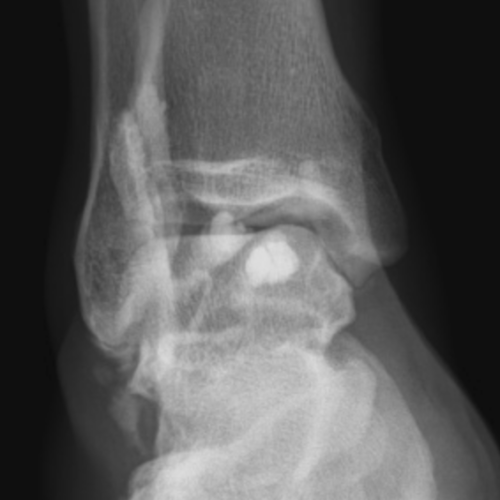

Polyarthrite Rhumatoide Radiographie Du Pied

Polyarthrite Rhumatoide Imaging Consult